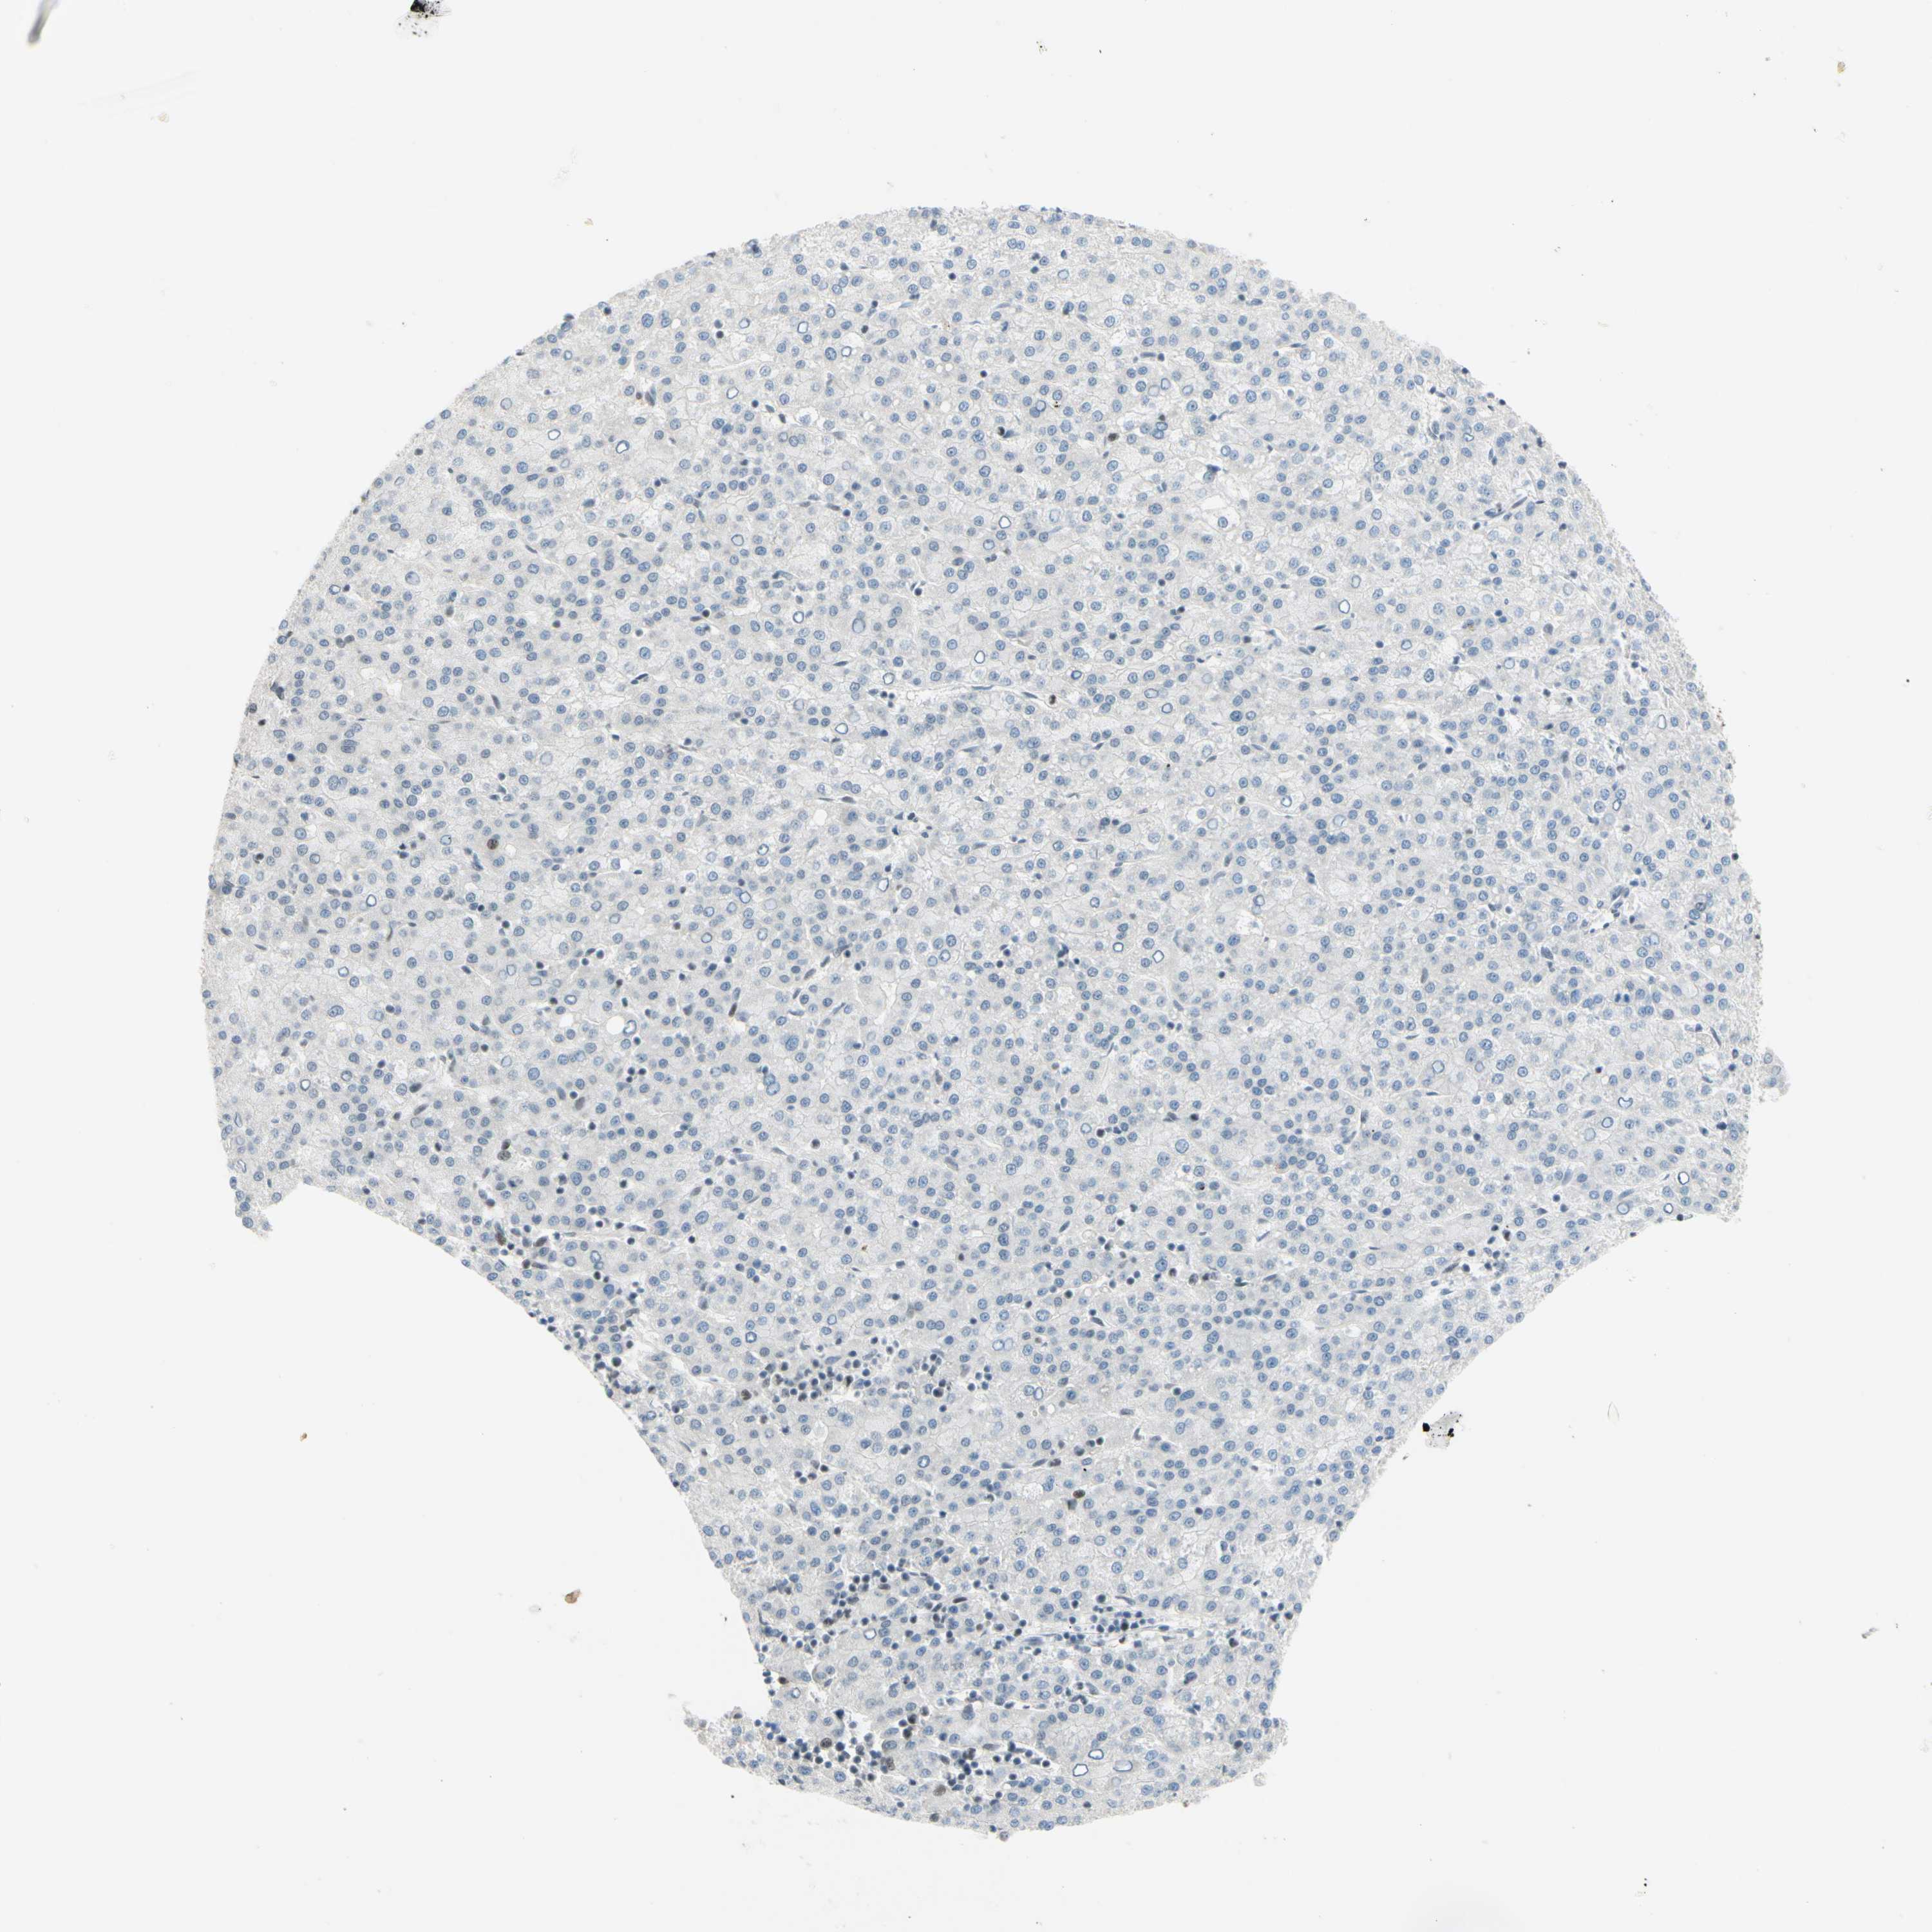

LIVER CANCER - Protein expressioni

A mouse-over function shows sample information and annotation data. Click on an image to view it in a full screen mode. Samples can be filtered based on level of antibody staining by selecting one or several of the following categories: high, medium, low and not detected. The assay and annotation is described here.

Note that samples used for immunohistochemistry by the Human Protein Atlas do not correspond to samples in the TCGA dataset.

Antibody stainingi

Antibody staining in the annotated cell types in the current human tissue is reported as not detected, low, medium, or high, based on conventional immunohistochemistry profiling in selected tissues. This score is based on the combination of the staining intensity and fraction of stained cells.

Each image is clickable and will lead to virtual microscopy that enables deeper exploration of all samples and also displays staining intensity scores, fraction scores and subcellular localization as well as patient and tissue information for each sample.

Antibody HPA008700

Staining

High

Medium

Low

Not detected

Intensity

Strong

Moderate

Weak

Negative

Quantity

>75%

75%-25%

<25%

None

Location

Nuclear

Cytoplasmic/membranous

Cytoplasmic/membranous,nuclear

Cholangiocarcinoma

Carcinoma, Hepatocellular, NOS